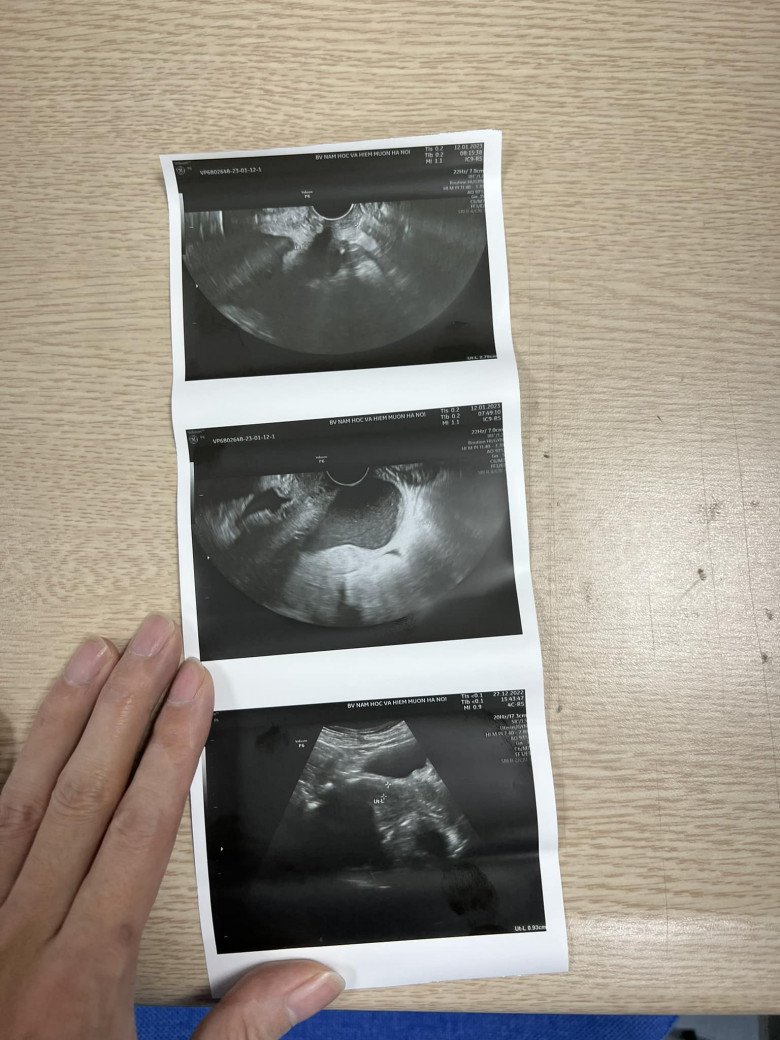

“Ngày 10/1/2023 vừa qua, chị Hà đi khám ở phòng khám ngoài thì được thông báo cổ tử cung ngắn nhiều nguy cơ sinh non nên ngay trong tối ấy chị vội vàng vào viện luôn. Khi tới viện, bác sĩ trực siêu âm cho biết, cổ tử cung của chị Hà đo chỉ được 22mm nhưng đã mở 2cm, ối gần ra ngoài”, bác sĩ Khanh nói.

Khi sang tới viện, các sĩ trực siêu âm cho biết, cổ tử cung của chị Hà đo chỉ được 22mm nhưng đã mở 2cm, ối phồng bằng quả quýt. (Ảnh: BSCC)